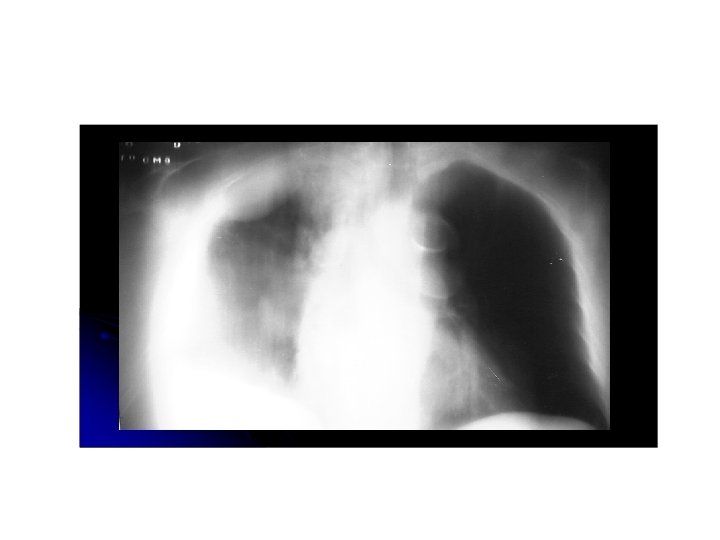

Carcinoma de celulas pequeñas • Altamente asociado a tabaquismo 10 -15% de cancer de pulmón. • Sospechar ante un hilio pulmonar aumentado de tamaño. • sin tratamiento, la sobrevida es de 2 -4 meses. • Mas común de localización central.

Enfisema centrolobulillar. Infiltrados intersticiales. Masa parahiliar izqueirda.

Masa hiliar lobulada con infiltrados interticiales y compromiso del bronquio intermedio. Atelectasia .